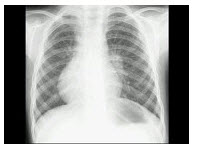

7、单项选择题

患者,女,28岁,轻咳两月,有盗汗。胸片如图:

A.Ⅰ

B.Ⅱ

C.Ⅲ

D.Ⅳ

E.Ⅵ